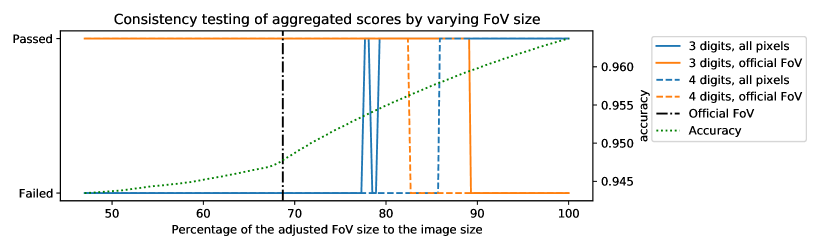

3.3.2 Sensitivity of the image level consistency test

To quantitatively characterize the sensitivity of the test to changes in the region of evaluation, we carried out a simulation treating annotation #1 as ground truth and annotation #2 as segmentation for all 20 images in the DRIVE test set. The FoV masks were gradually dilated to cover the images; for each mask size, the performance scores were calculated and rounded to 3 and 4 digits; and the tests derived in subsection 3.3.1 were applied to the scores to check whether they were computed under the original FoV masks or using all pixels of the images. The percentages of image level scores passing the tests at certain mask sizes are plotted in Figure 2 along with the average accuracy to illustrate the bias caused by the adjustment of evaluation region. The first thing to observe is that varying the size of the evaluation region has a remarkable effect on the accuracy scores. However, when the performance scores are rounded to 4 digits, a deviation as little as 1% from the assumed region makes the test fail on more than 50% of the 20 test images, as can be seen by the steep drop in the corresponding dashed lines around the size of the official FoVs (69% of the image size) and at 100% of the image size. The increased uncertainty of rounding to 3 digits widens the acceptance window (solid lines) and about 50% of the scores pass despite a 15% change in the size of the evaluation region. However, the passing rate drops to about 5% at the opposite assumptions, indicating that the two edge cases can still be distinguished by the test. The analysis suggests that the consistency test is able to distinguish the cases where the official (or slightly differing) FoV masks were used from those cases when all (or almost all) pixels of the images were included in the evaluation.

3.4.2 Sensitivity of the consistency test for aggregated figures

Similarly to the image level analysis, the aggregated figures must pass the test if the assumptions are met. However, due to the increased numerical uncertainty, it is questionable whether the sensitivity of the test is high enough to distinguish the two corner cases we are concerned with. As before, a quantitative characterization of sensitivity can be obtained by varying the size of the evaluation region, but this time checking whether the aggregated figures pass the test with the , , numbers extracted according to the hypotheses. According to the results shown in Figure 4, a 15% deviation in size from the hypothesised region causes the test to fail when the scores are reported to 4 digits. With rounding to 3 digits, the two corner cases are still distinguished by the test. However, if the region of evaluation is between 77%-87% of the image size, the scores can pass the test with either assumption.